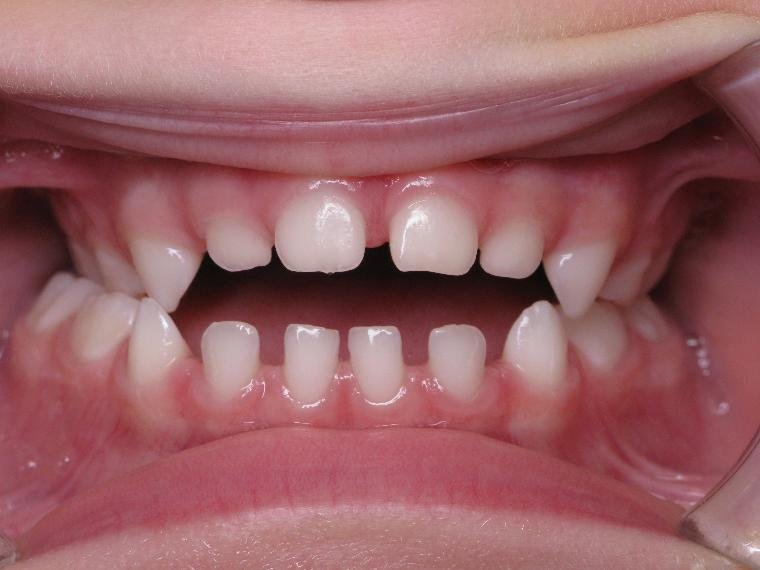

inversion postérieur coté droit et espace entre les dents du haut et du bas (diastèmes)

appareillage mobile pendant 35 mois

surveillance évolution de la dentition pendant 5 ans